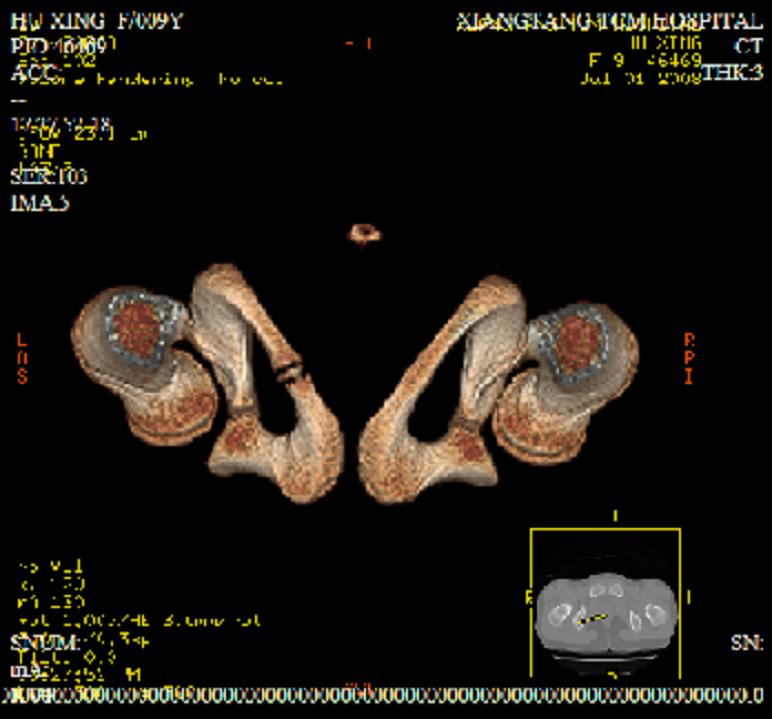

以下是引用zxd95在2008-7-2 10:06:00的发言:[br]左耻骨下支局部骨质破坏,内见小条状小骨片,周围肌间隙模糊,左闭孔内外肌肿胀。[br]儿童患者,首先考虑结核性,以骨质破坏为主(其内小条状小骨片解释为死骨)。[br]鉴别:[br]1、化脓性病变以增生为主;[br]2、肿瘤性病变:良性肿瘤不会有周围软组织的肿胀、模糊;恶性肿瘤病变骨皮质破坏、中断;[br]3、肿瘤样病变:一般也无周围软组织的改变。[br]建议查肺部及结核相关实验室检查。